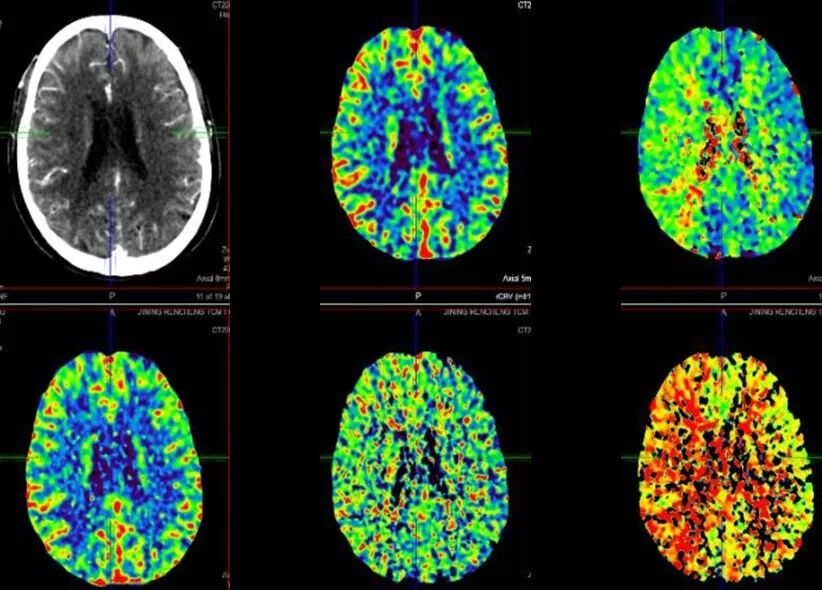

入院影像检查

导丝怎么扩【载药时代 球扩天下】NOVA DES®颅内药物洗脱支架在颈内动脉颅内段重度狭窄的应用二例!_https://www.jmylbn.com_新闻资讯_第8张

2022-7-17 颅脑DWI

2022-7-17 颅脑MRA

导丝怎么扩【载药时代 球扩天下】NOVA DES®颅内药物洗脱支架在颈内动脉颅内段重度狭窄的应用二例!_https://www.jmylbn.com_新闻资讯_第9张

导丝怎么扩【载药时代 球扩天下】NOVA DES®颅内药物洗脱支架在颈内动脉颅内段重度狭窄的应用二例!_https://www.jmylbn.com_新闻资讯_第10张

2022-7-20 颅脑CTP

重要影像结论:右侧放射冠区新发脑梗死,右侧颈内海绵窦段重度狭窄,右侧大脑半球缺血。

导丝怎么扩【载药时代 球扩天下】NOVA DES®颅内药物洗脱支架在颈内动脉颅内段重度狭窄的应用二例!_https://www.jmylbn.com_新闻资讯_第11张

导丝怎么扩【载药时代 球扩天下】NOVA DES®颅内药物洗脱支架在颈内动脉颅内段重度狭窄的应用二例!_https://www.jmylbn.com_新闻资讯_第12张

重要影像结论:右侧大脑半球缺血。